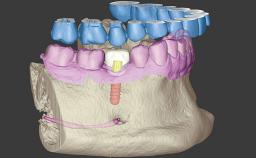

Professor Dr. Joda is Head of Dental eHealth & Digital Technology at the Clinic of Reconstructive Dentistry, University of Zurich, Switzerland. He is Principle Investigator and actively participates in clinical and translational research related to implant workflows and prosthetic treatment concepts in the field of digital dental technologies and e-health data management using AI and ML.